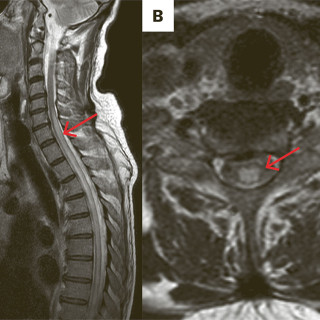

Denne kasuistikken beskriver alvorlig iatrogen botulisme etter behandling med injeksjon av botulinumtoksin ved en privatklinikk i utlandet. En kvinne i 40-årene ble akuttinnlagt i medisinsk avdeling grunnet økende svelgparese, svakhet i nakkemuskulatur, obstipasjon, munntørrhet, hodepine, fatigue, tunge øyelokk og uklart syn de siste fem dager. De siste tre dagene før innleggelsen hadde hun ikke fått i seg flytende eller fast føde, og hodet måtte støttes når hun skulle sette seg opp. Det fremkom at hun 15 dager tidligere hadde fått injisert botulinumtoksin type A mot migreneplager under et...